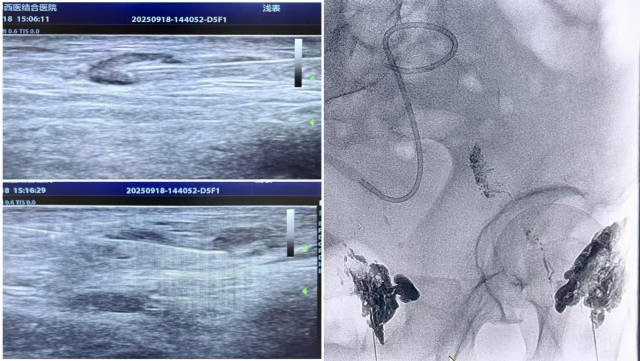

1、淋巴管精准造影:在超声实时引导下,医疗团队精准定位患者双侧腹股沟淋巴结,采用 22G 细针穿刺至淋巴结皮质与髓质交界处,缓慢注射造影剂。随后借助数字减影血管造影(DSA)技术,动态追踪淋巴液流动轨迹,精准锁定乳糜漏口位置。

2、漏口栓塞封堵:根据漏口大小与位置,选用碘油单独或与组织胶按特定比例混合,缓慢注入漏口区域,通过物理栓塞作用阻断异常淋巴液渗漏,恢复淋巴系统正常循环功能。

淋巴结造影+栓塞